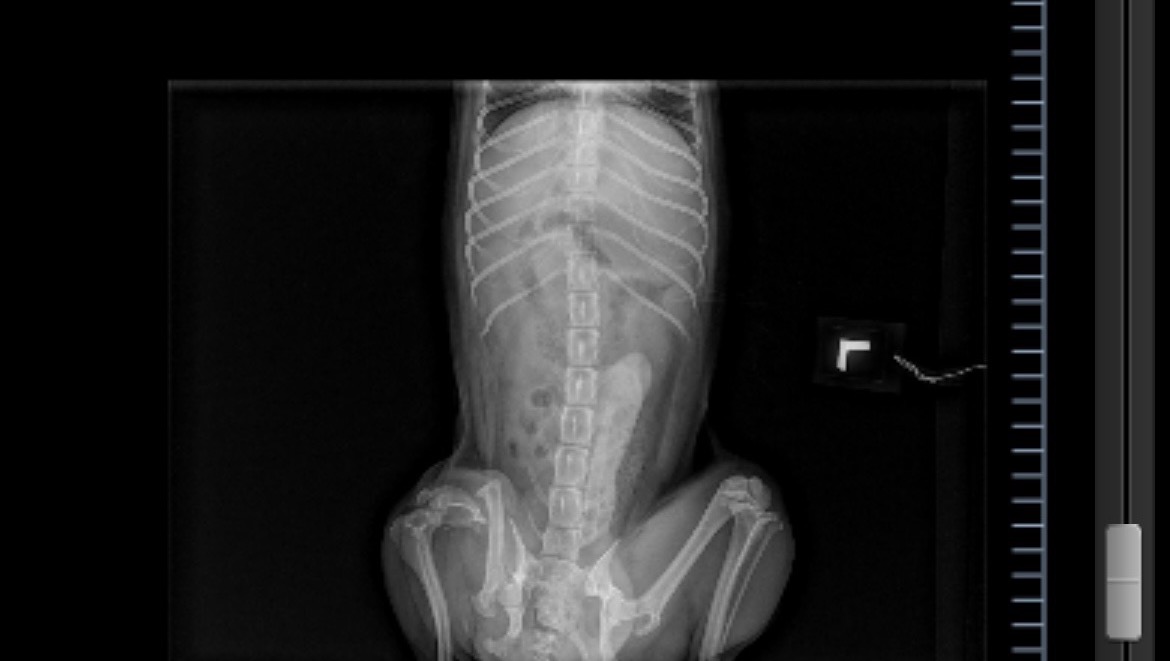

We adopted Dobby on 2/5/22 from the high-kill Baldwin Park animal shelter, where he was brought in as a stray on 1/30/22. Right away, the staff noticed that he wasn’t putting any weight on his rear right leg. Soon after, it was discovered that he had a pretty significant injury, but no way to tell how long he’s had it for.

As soon as we met him, we fell in love. He has the sweetest and most calm demeanor I’ve ever seen in a small breed, and it was obvious that he’d spent quite a bit of time on the streets because he wasn’t afraid of loud traffic, or any outside noises while we were out. We also kind of suspect that he may have been used in backyard breeding, because he wasn’t neutered. The vets we’ve seen so far estimate that he’s anywhere from 4.5-6 years old, but they can’t tell how long he’s had a broken leg.

The lovely surgeons at Inland Empire Veterinary Surgical Specialty advised us that amputation will be the best option. The total cost of his leg surgery and neuter come out to $3600, and so far every vet we’ve talked to is recommending that the neuter is done at the same time as the amputation (with the anesthesia and all), that’s why he wasn’t neutered at the shelter. Thankfully, his surgeon confirmed that he doesn’t really experience any pain, a sign that it may be old/healed, so we have time to plan for this financially, as well as prepare him for the healing process.